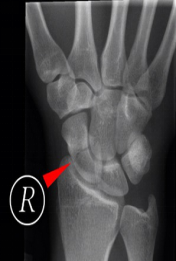

掌骨骨折;指骨骨折;手舟骨骨折

舟月骨缺血性坏死

腕关节发生骨缺血坏死的常见部位为舟骨和月骨

好发于20-30岁手工劳动者,也常见于腕部急性创伤和月骨骨折脱位后

男性多见

X线表现为病变早期骨形态尚可,骨质密度增高,其内可见囊样透亮影,进展期骨质塌陷,周边关节间隙增宽;MR对早期骨缺血坏死较敏感

舟骨缺血性坏死

54Y,M 月骨缺血性坏死